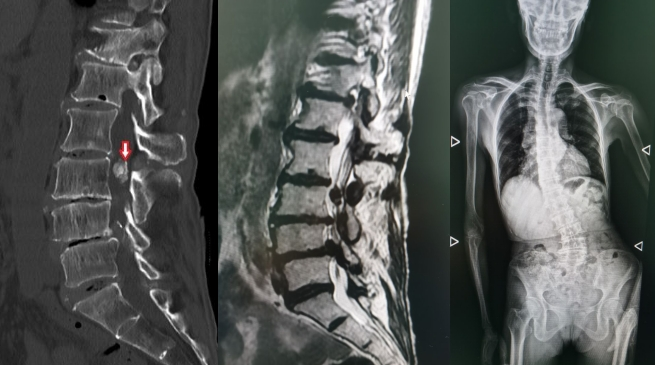

卿培东主任安排李女士进行了腰椎电子计算机断层扫描(CT)检查。检查结果显示,李女士的腰2-3硬膜内有肿物占位,腰3-4及腰4-5椎管狭窄并伴有脊柱侧弯。

卿培东耐心给李女士及其家人解释:“从影像学检查结果看,您的硬膜内的肿物较大,无法确定是肿瘤还是其他病变,但结合临床症状看,肿物对脊髓的压迫已经十分严重了,如不及时采用手术治疗,随着病程发展,您肢体无力、麻木疼痛的症状会加重,甚至可能导致瘫痪。”

卿培东说:“这次手术为李女士进行了硬膜内肿物切除,腰椎管狭窄神经减压和脊柱侧弯矫形,可谓‘一举三得’。术后病理检查证实,李女士硬膜内的肿物为痛风石样结晶。”